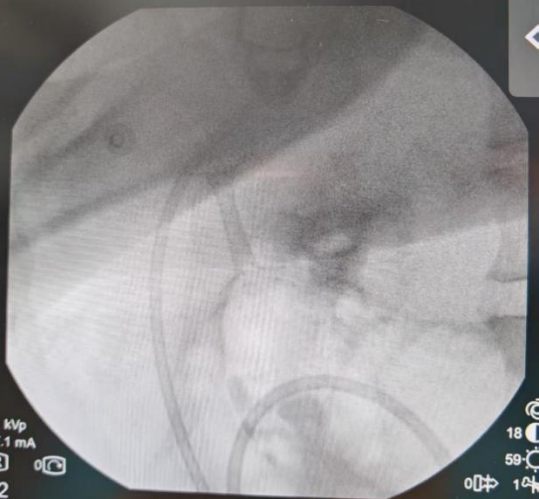

导丝、切开一气呵成,通道建立。一枚胰腺WON专用引流支架(LAMS)被成功置入,即刻可见大量液体流出至胃腔内。但李阿姨的坏死腔巨大,内容物黏稠。如果只用单支架,一旦堵塞或移位,效果将大打折扣。

手术过程流畅,即刻见大量坏死液顺利引流。术后第三天,CT复查结果令人振奋,坏死包裹从13厘米显著缩小至9厘米,胃部压迫得到有效缓解。

红色为坏死性包裹,蓝色箭头为支架